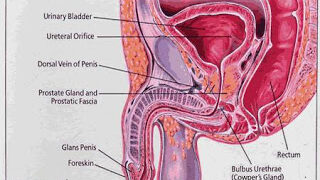

Read moreডা. মিজানুর রহমান কল্লোল প্রস্টেট হচ্ছে ছোট একটি গ্রন্থি, যা পুরুষদের থাকে। এটির অবস্থান মূত্রথলির ঠিক নিচে। প্রস্টেট ঘিরে রাখে...